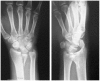

Background: The aim of this study was to compare the functional outcomes and complications of volar and dorsal plating for the management of intra-articular distal radius fractures, with special regard to indications for dorsal plating. Furthermore, we examine the rationale for choosing dorsal plating and its frequency of use.

Methods: Clinical assessments included range of motion measurements at the wrist; grip strength; the Quick Disabilities of the Arm, Shoulder, and Hand score; and the Gartland and Werley score. Clinical results were compared with those achieved using a volarly placed locking plate system. According to Lutsky's plate theory, the rationale for choosing dorsal plating was based on 4 types of pathologic fractures.

Results: Of 112 patients, 38 patients were treated with open reduction internal fixation via a dorsal approach and 68 patients were treated using a volar approach. Except for wrist flexion, there were no other statistical differences in the clinical results between groups for both subjective and objective parameters. There were no statistically significant differences in the complication rates between the volar and dorsal plated groups. One serious complication occurred after volar plating. The most common reason for choosing dorsal plating was irreducible dorsal die-punch fractures.

Conclusions: The treatment of displaced intra-articular distal radius fractures with a dorsally versus a volarly placed interlocking plate system demonstrated similar clinical results. Postoperative complications were not readily observed in the patients treated with a dorsal locking plate. Certain fracture patterns are more appropriately stabilized using a dorsal plate fixation.